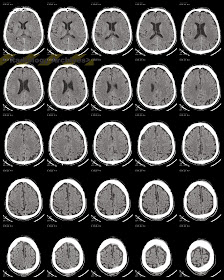

Κρανιοεγκεφαλική Κάκωση (Κ.Ε.Κ.)

1/ Γραμμοειδές Κάταγμα

Μετωπιαία Αριστερά 2/ Πάχυνση του

Βλεννογόνου του Σφηνοειδούς Κόλπου 3/

Αιμορραγικές Θλάσεις Κροταφικά Δεξιά & Υπαραχνοειδής Αιμορραγία 4/ Μικρό Υποσκληρίδιο Αιμάτωμα στο

Σκηνίδιο Δεξιά 5/ Ενδοεγκεφαλικό

Αιμάτωμα Μετωπιαία Αριστερά με Περιεστιακό Οίδημα 6/ Επισκληρίδιο Αιμάτωμα

Μετωπιαία Αριστερά 7/ Υποσκληρίδιο

Αιμάτωμα Μετωπιαία Αριστερά